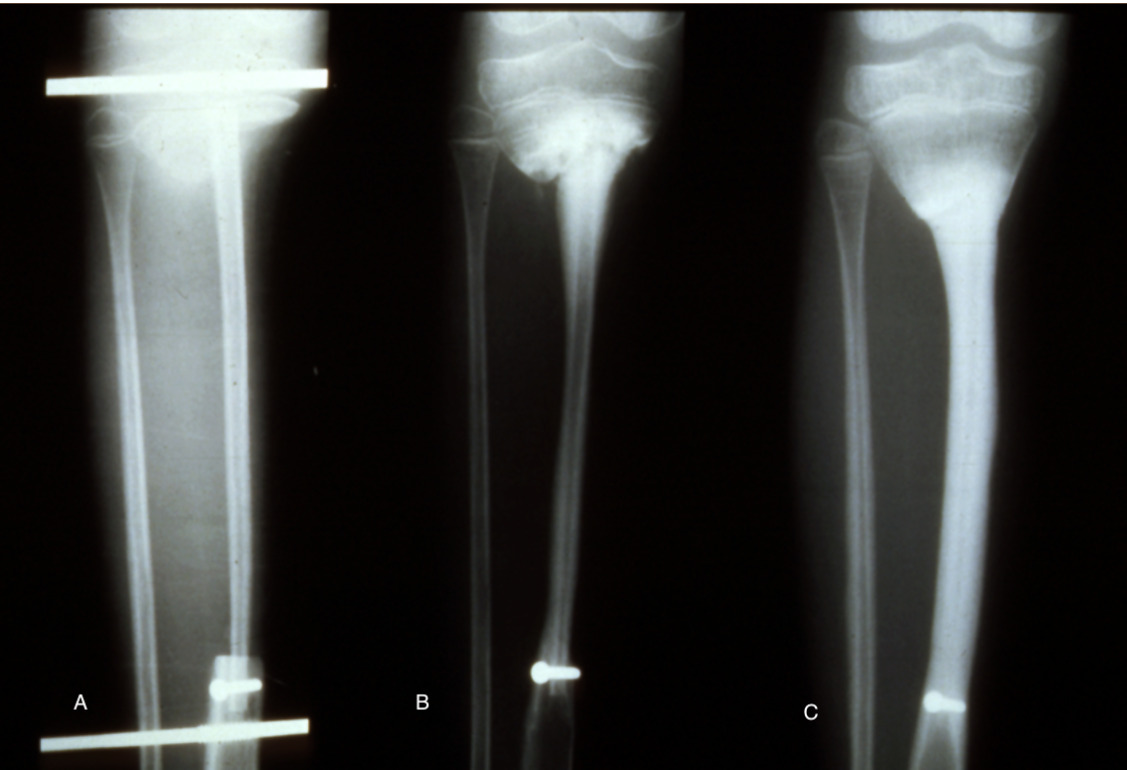

An 18 cm length of fibula was detached and transferred to bridge the 15 cm defect in the tibia. Periosteum was stripped from the distal end, dowelled into the tibia and secured with a screw. The proximal end was abutted against the underside of the growth plate of the tibia, balanced like a saucer on the end of a pole, and stabilised with an external fixateur (Figure 11A).

At three months the distal end of the fibula graft had united to the tibia. The fixateur was removed leaving behind the transfixing pins that were fixed into an above-knee plaster cast. At eight months the cast was removed, the limb placed in a caliper and weight bearing commenced. Union was noted at the upper end (Figure 11B). By two years dramatic hypertrophy of the transplanted fibula was noted together with growth from the proximal epiphysis (Figure 11C). The limbs had almost identical length (Figure 12), the knee and ankle joints were normal and the only disability was temporary weakness of the EDL in the donor leg.